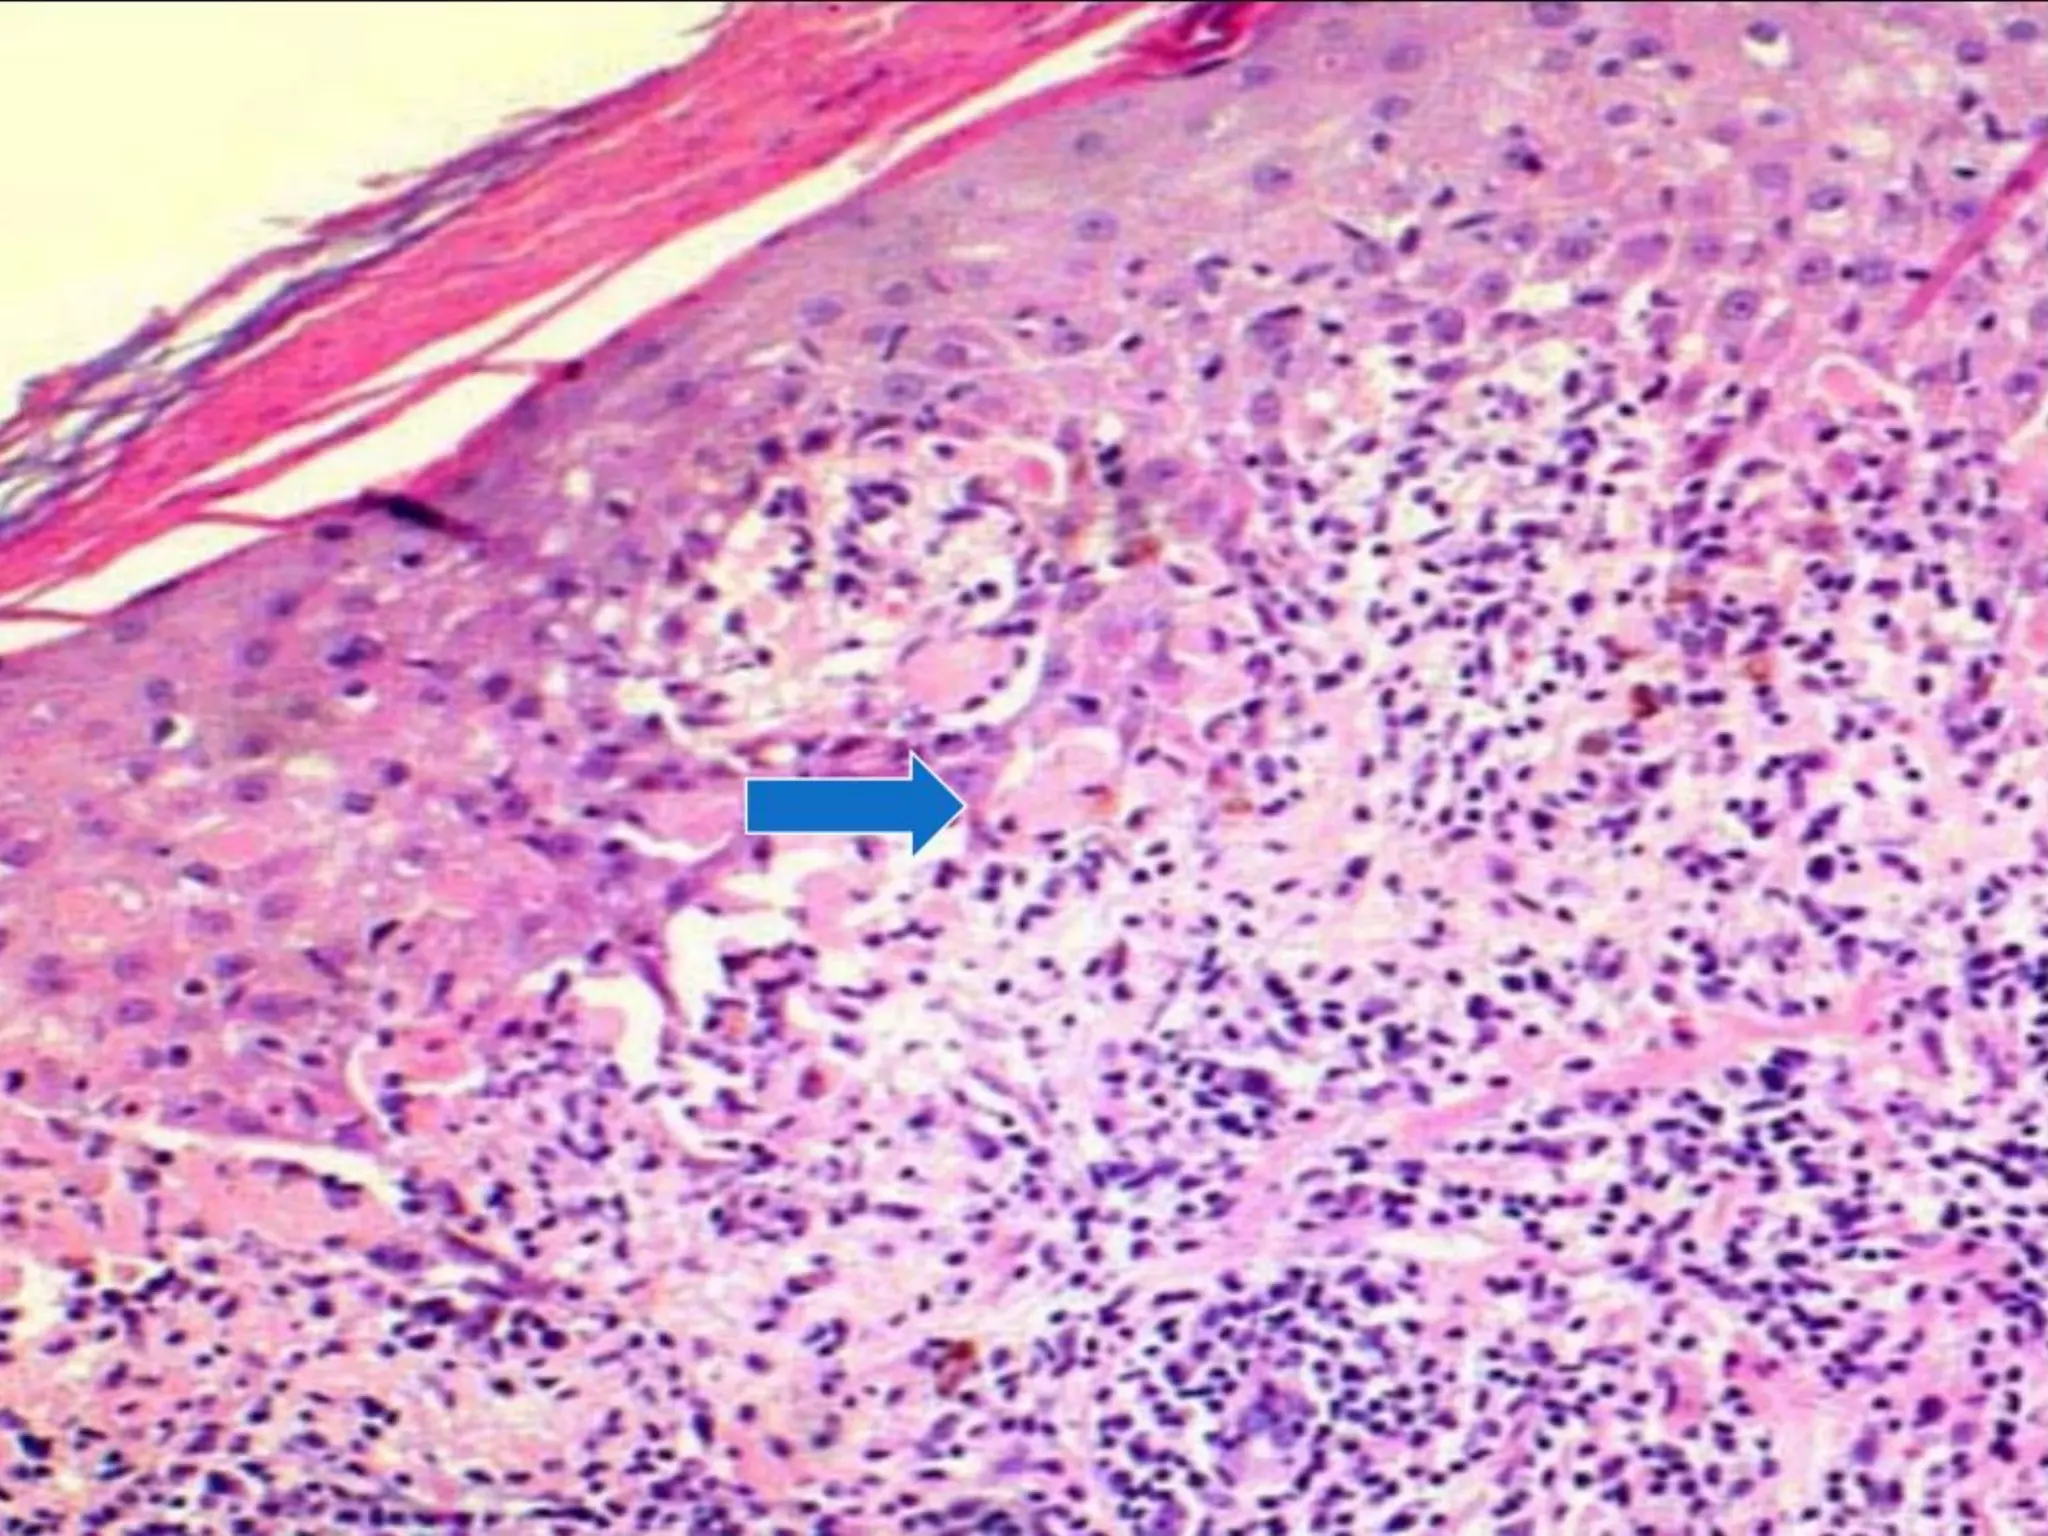

The document provides an overview of dermatopathology, including methods and techniques for skin biopsies such as shave, punch, and ellipse methods. It discusses key terms associated with dermatopathology, such as acantholysis and granulation tissue. Additionally, it references presentations by professionals in the field and essential dermatology resources.